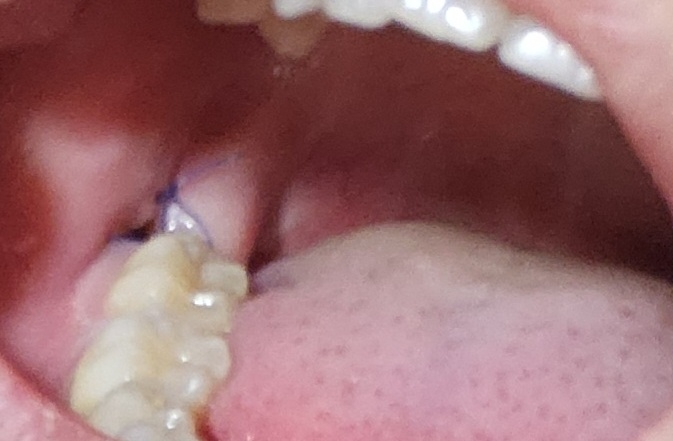

매복사랑니 발치 5일차 하얀게 생겼어요

매복사랑니 발치 후 5일차입니다.

• 1번 째 사진